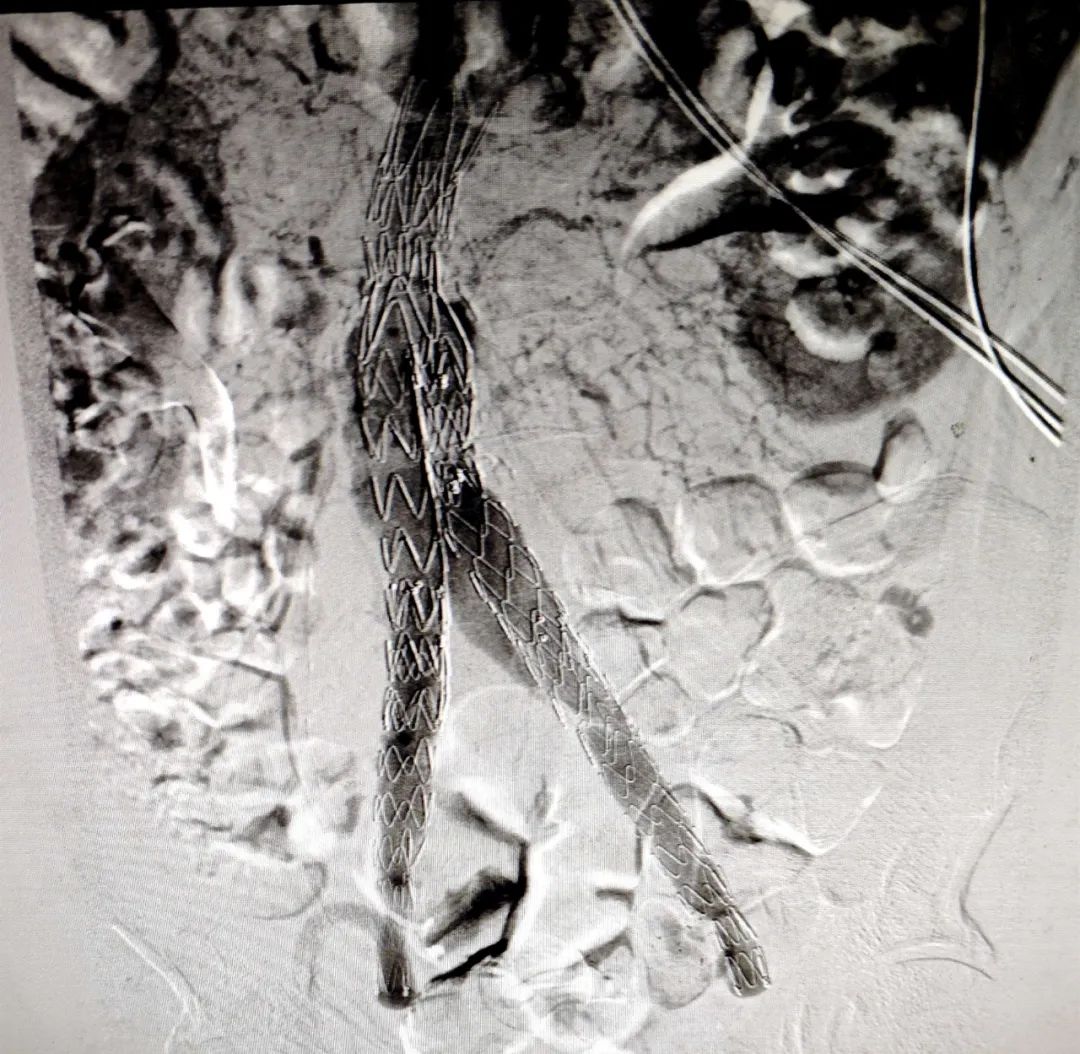

腹主动脉瘤病情凶猛,每耽搁一秒就有随时破裂的风险,使患者失去生命。在介入科代主任的带领下,经多学科专家会诊,反复讨论、评估,并与家属充分沟通后,决定采用覆膜支架腔内隔绝术进行治疗。覆膜支架腔内隔绝术,隔绝动脉瘤腔,重塑血管,解除动脉瘤璧受到的血流冲击并且保持腹主动脉管腔通畅。该疗法从根本上防止腹主动脉破裂,避免发生致死性大出血。

支架植入术后血管重塑